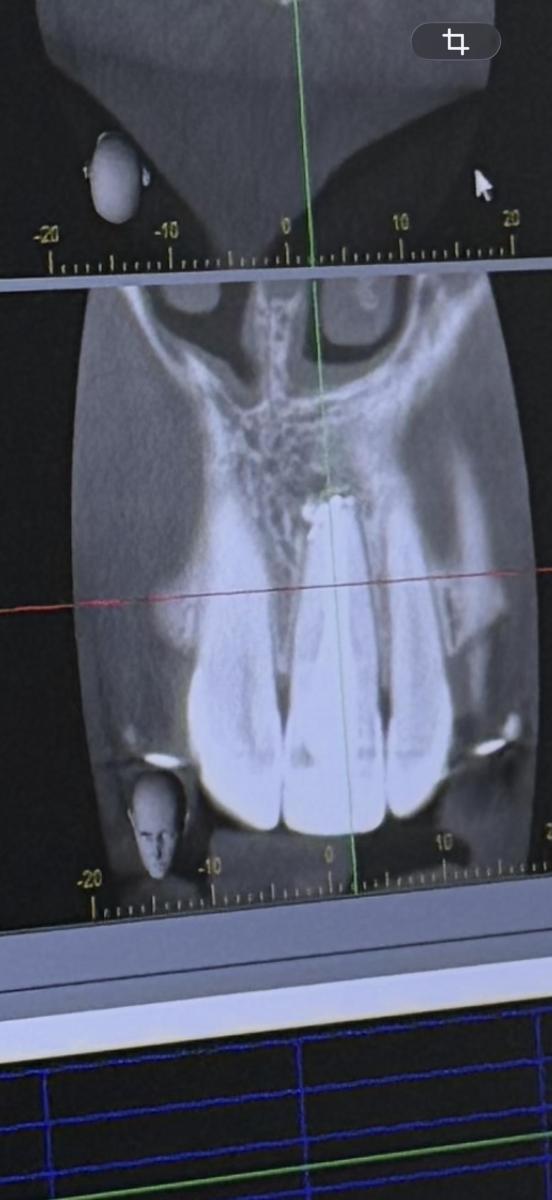

Такой вопрос. Почему может болеть зуб? Каналы пролечены. Лечили повторно 1 год назад. Сейчас начал болеть зуб. Зуб после травмы. Боль ноющая, при постукивание и нажатие не болит. Снимок 1 после пол года лечения, 2 после года лечения. После последнего снимка прошел месяц и зуб начал болеть.

качество ужасное. В хорошем загрузить не удалось

Вот полный снимок. Может смотрится что на том зубе кариес потому что дуга от брекетов засвечивает.